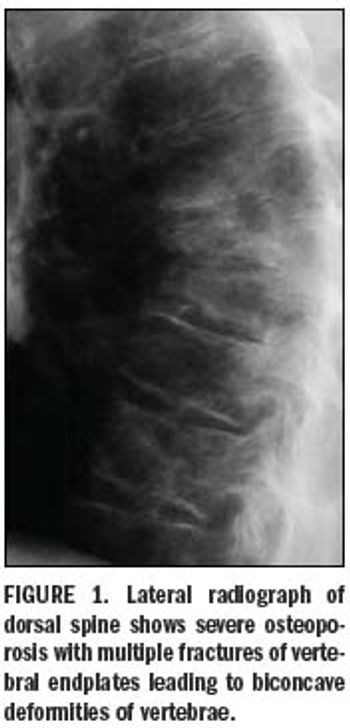

Imaging tools transform diagnosis of osteoporosis

Bone mineral density measurements of the axial and appendicular skeleton are an important part of the diagnosis and follow-up of metabolic bone disease.